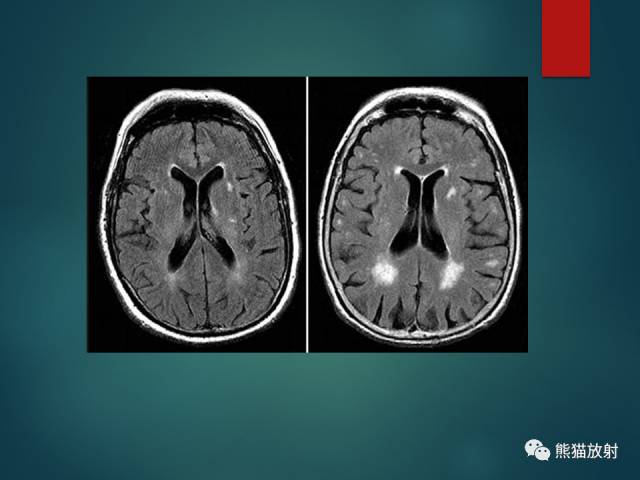

- 脑白质疏松(LA):小动脉病变导致的白质纤维脱髓鞘;T2-FLAIR呈较高信号,DWI无弥散受限;常两侧对称,脑室周围明显。

- 腔隙性脑梗死(LACI):颅内小动脉及穿支动脉狭窄或痉挛;T2-FLAIR呈高信号;DWI急性期弥散受限;基底节、脑干及丘脑多见。